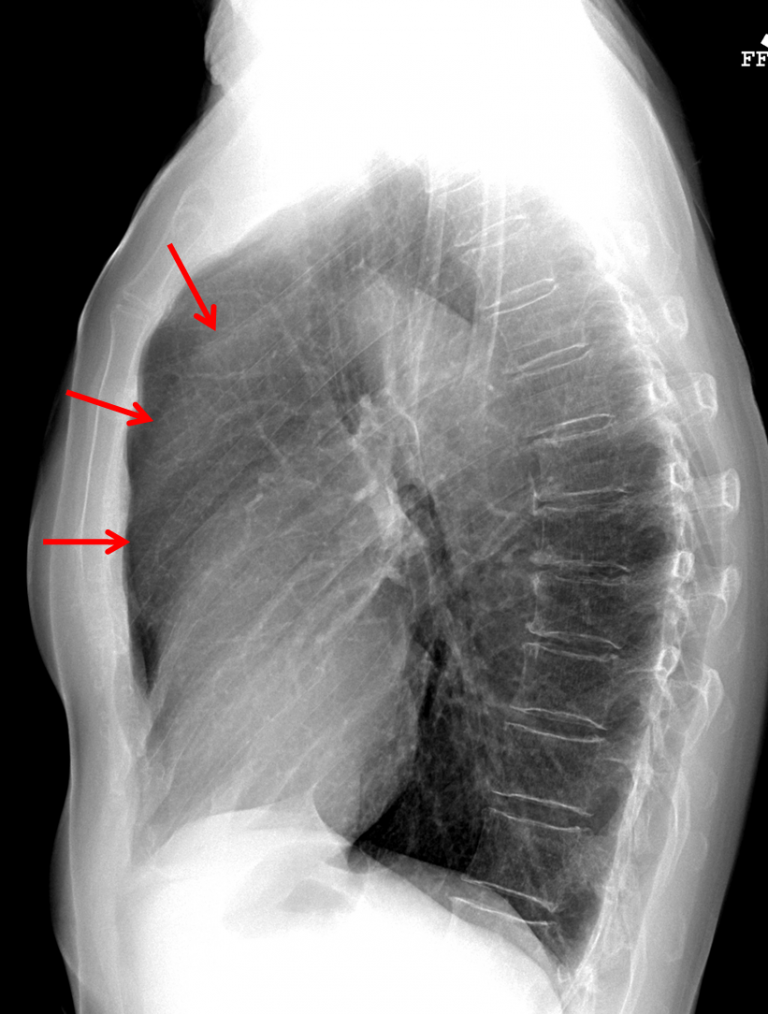

Age: 83

Sex: Female

Indication: Chest pain

Sample ReportFindings concerning for dilation of the ascending aorta, which could relate to aneurysm or dissection. Consider chest CTA for further evaluation.